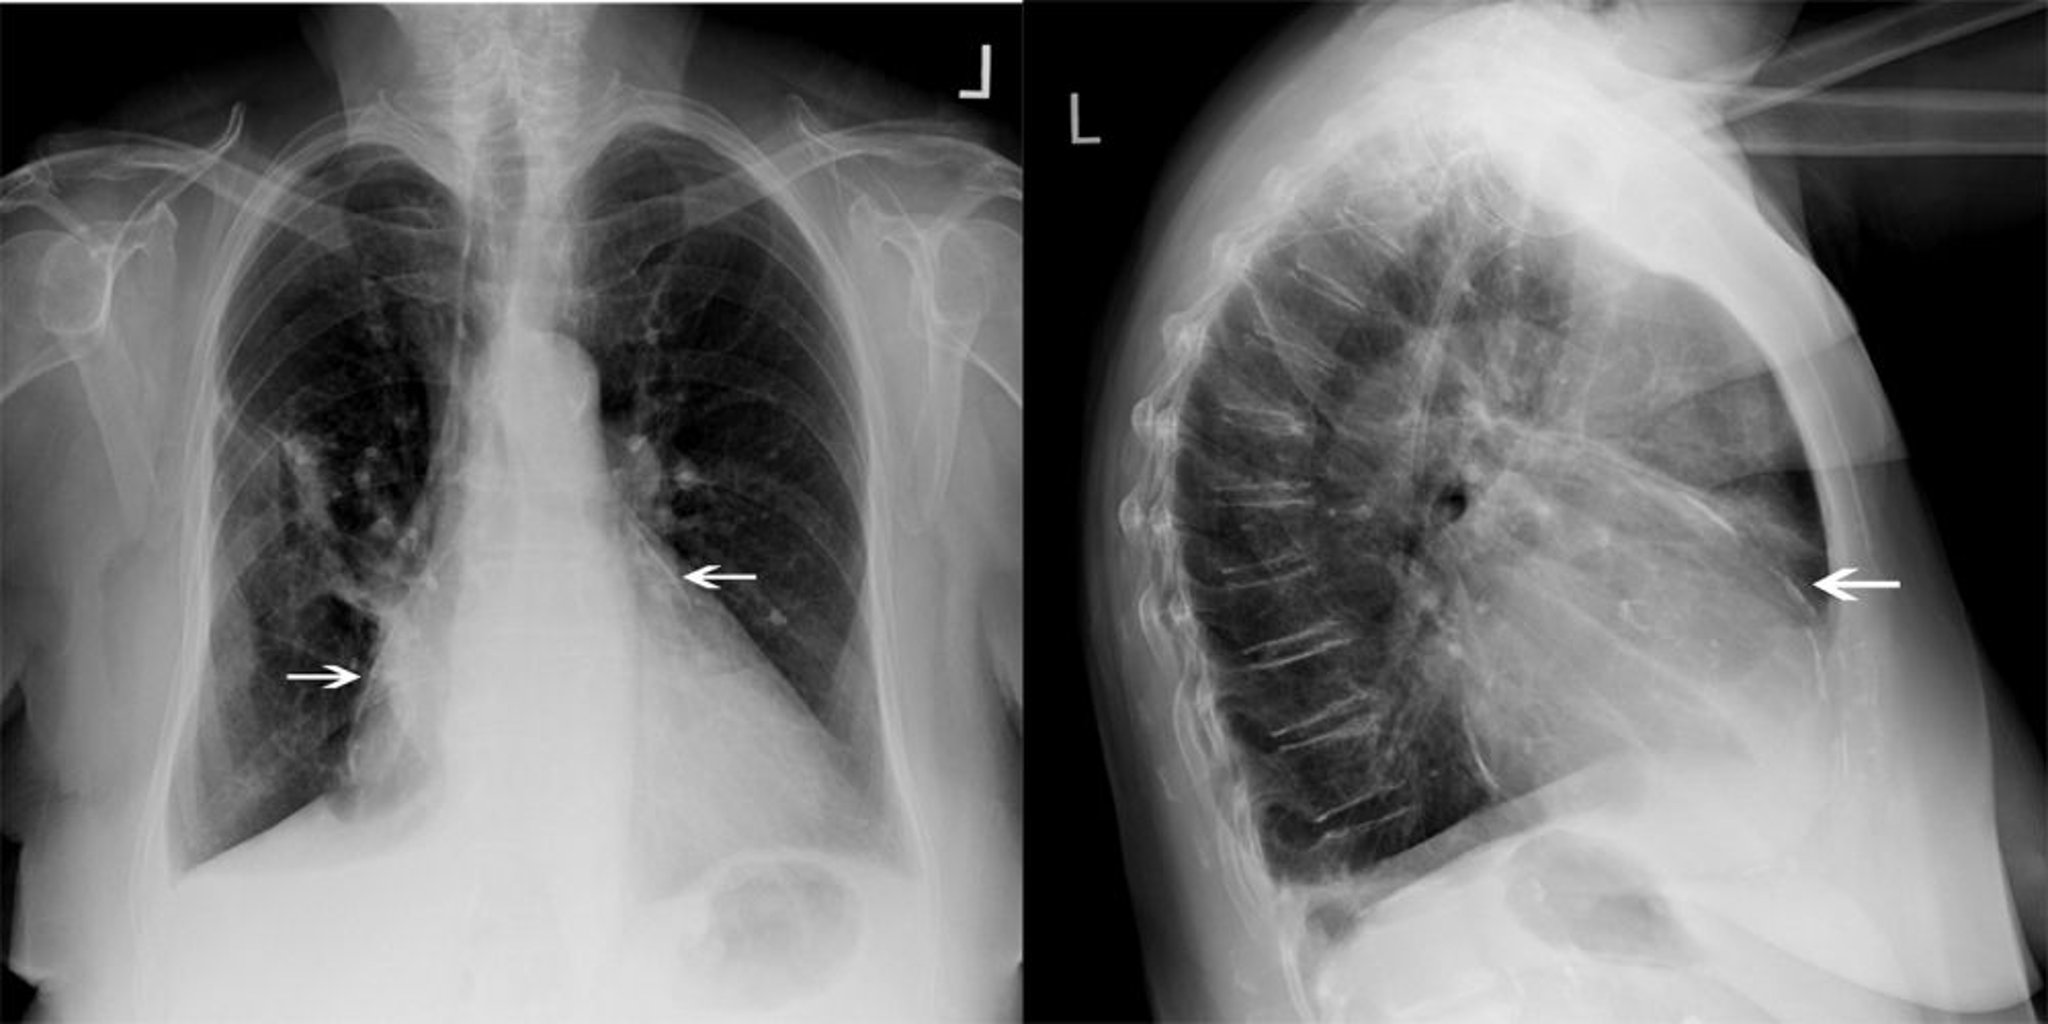

Radiografía torácica de un paciente con pericarditis constrictiva

Este paciente con pericarditis constrictiva tiene una calcificación pericárdica significativa (flechas blancas).